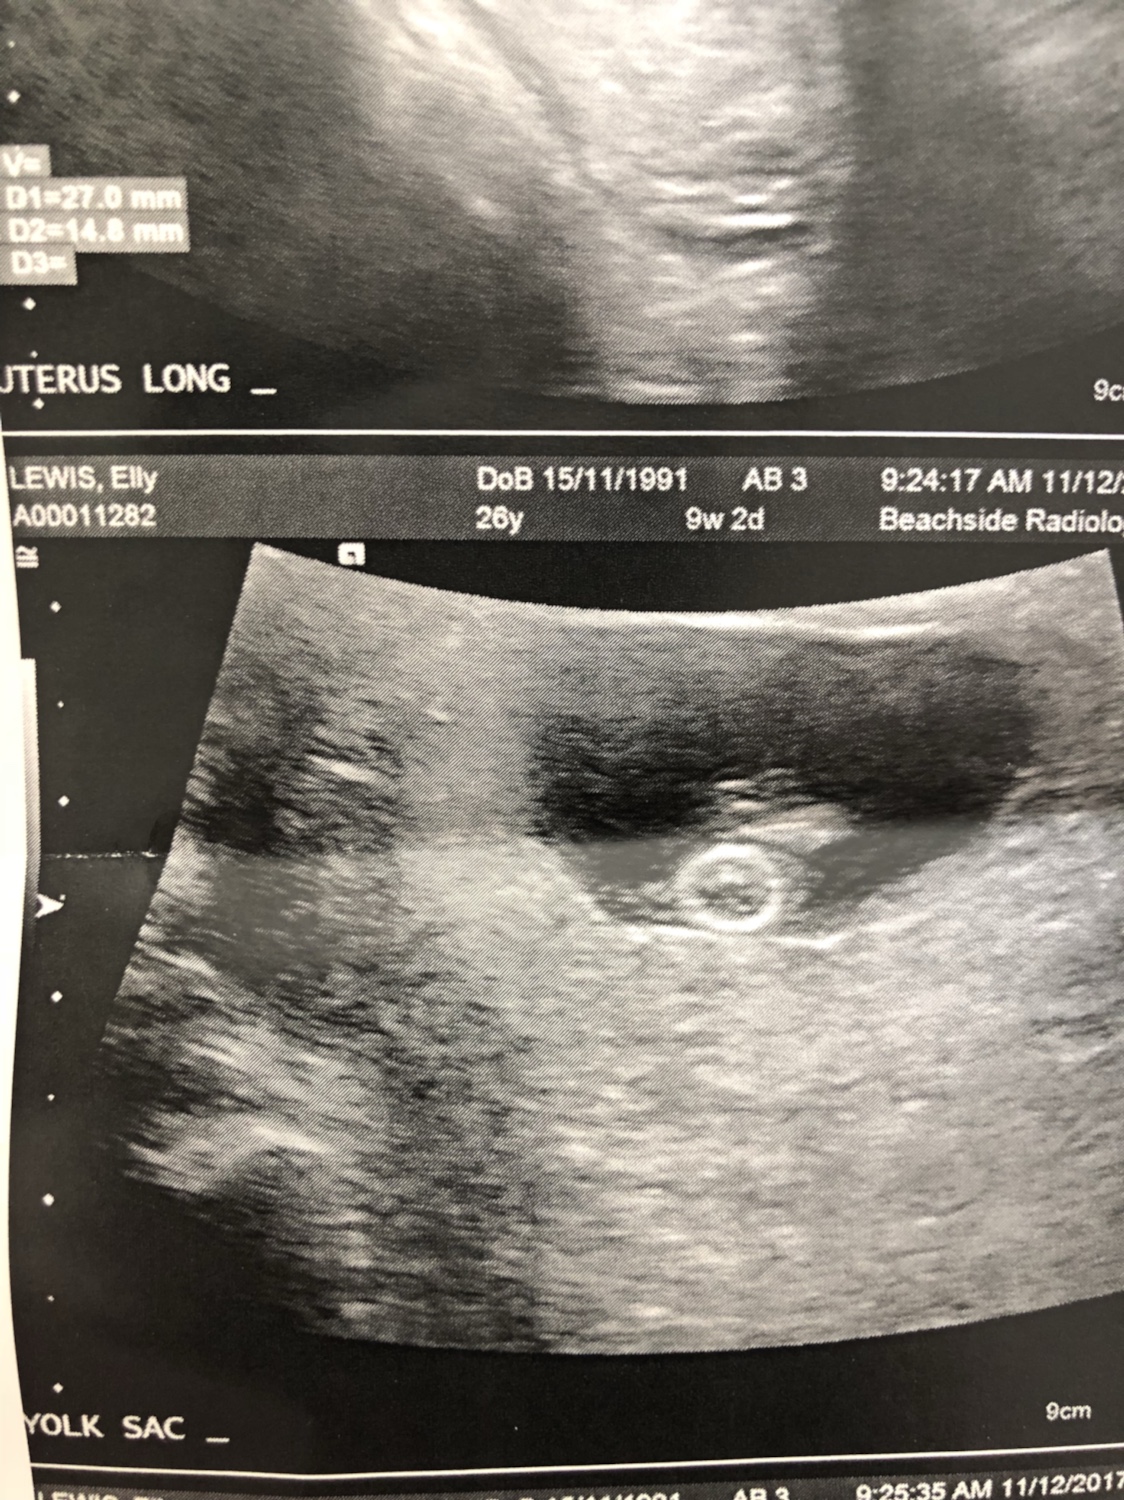

So I’m 8 weeks and 1 day today and I had my scan. It was abdominal not vaginal so I know that sometimes it can be flipped. I completely forgot to ask what side the placenta was on so fingers crossed someone can give me an idea on what I’m looking at! Thanks

Attachment 38386Attachment 38387Attachment 38388